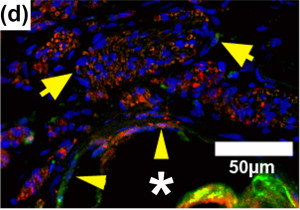

Figures A-D: Immunostained regenerating tissues after 6 weeks; (a and b) mid-conduit sections were stained for GLUT1 (green)/S100 (red)/DAPI (blue) in (a) NoMgSa and (b) MgSa animals (*cavity left by Mg, arrows delineate conduit material, bar=300μm). (c and d) Regenerating nerve mini-fascicles, indicated by arrows, run close to the Mg cavities, which are marked by * and arrowheads. The same staining was done on the section in (c), while the section in (d) was stained with ED1 (green)/NF200 (red)/DAPI (blue). Note GLUT1þ perineurium in (c) and thin layer of ED1+ macrophages above arrowheads in (d) (bar in c and d=50μm).

NoMgSa: saline filler only; MgSa: saline and Mg; GLUT1: glucose transporter 1; DAPI: 4’ 6-diamidino-2-phenylindole.2